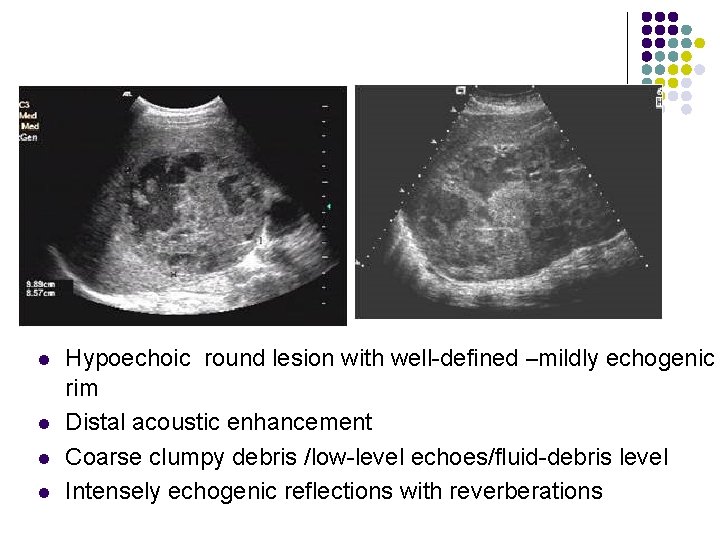

Hepatic abscess- l l Hypoechoic round lesion with well-defined –mildly echogenic rim Distal acoustic enhancement Coarse clumpy debris /low-level echoes/fluid-debris level Intensely echogenic reflections with reverberations

l l Hypoechoic round lesion with well-defined –mildly echogenic rim Distal acoustic enhancement Coarse clumpy debris /low-level echoes/fluid-debris level Intensely echogenic reflections with reverberations